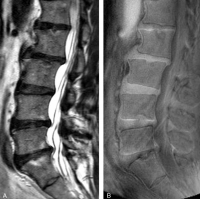

MRI of the lumbar spine of a subject with no chronic low back pain.

(Left) T2-weighted MRI noting multilevel disc degeneration and Modic changes.

(Right) Ultra-short time-to-echo (UTE) MRI noting no UTE disc sign (UDS).